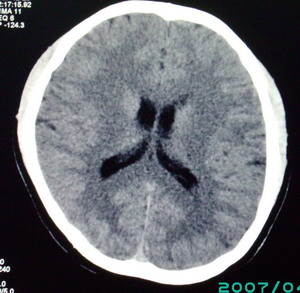

以下是引用九目段在2007-12-24 14:55:00的发言:[br]1,年轻女性[br]2,ct表现:左侧脑室三角区可见一不规则小明显强化的结节,中央见小低密度,侧脑室无扩张。[br]分析:[br]常见的有三种肿瘤好发三角区:[br]1,脉络丛乳头状瘤,好发于年轻者,明显强化,实性,分泌脑脊液,常伴有侧脑室扩大,肿瘤较小可以脑室扩大不明显,不能排除,但小结节尚不易形成坏死腔。[br]2,室管膜瘤,好发于儿童及青少年,明显强化,易坏死,大时伴脑室扩张。[br]3,脑膜瘤,明显强化,圆形,界请,无脑积水,一般不坏死。[br]诊断:[br]左侧脑室三角区结节,考虑室管膜瘤可能性大,不排除脉络丛乳头状瘤和脑膜瘤(因病史较长)。[br][br][本贴已被 九目段 于 2007-12-24 15:13:35 修改过]